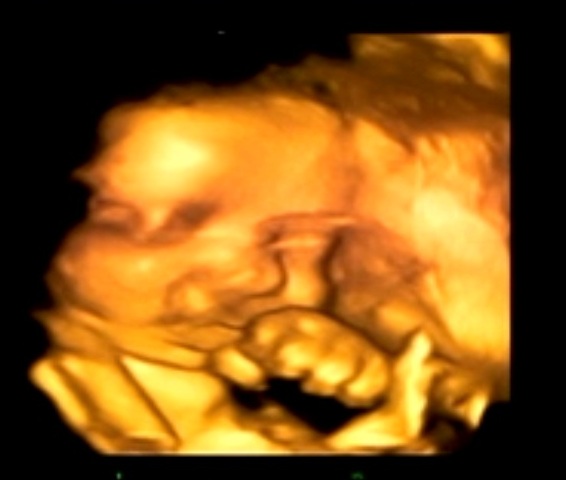

PS: A foto acima é do último utrasom, feito no início do mês. A Clara estava com 32 semanas, 1.800kg e 42cm.